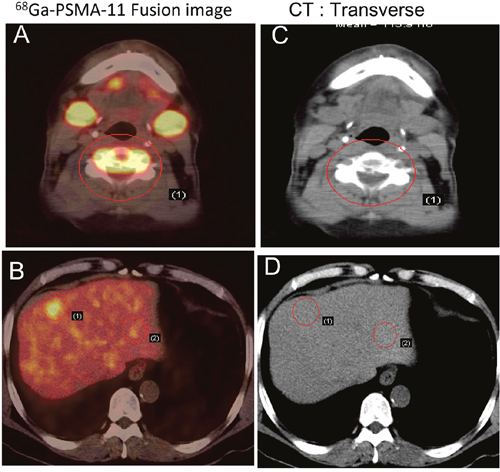

In 29 patients with bone metastasis, SUVmax ranged from 3.00 to 124.71 (27.57 ± 27.46). In 3 patients with stable disease, the PSA values ranged from 0.01 to 0.07 ng/ml, and no 68Ga-PSMA-11 uptake was observed, including into osteoblastic bone lesions. Of the 22 patients with treatment-naïve PCa, 17 had multiple lymph node and bone metastases. Based on these findings, these patients initially received hormonal treatment and radiotherapy or chemotherapy. For those with only pelvic lymph node positivity, radiotherapy was considered depending on the magnitude of PSA decline after hormone deprivation. In one patient with spinal cord involvement (SUVmax = 124.71), multiple lymph node and bone metastases were found in 68Ga-PSMA-11 images (Figure 3). In addition, 68Ga-PSMA-11 PET/CT newly detected lung metastasis in 5 patients and liver metastasis in 4 patients (Figures 4 and 5). In total, 17 patients with treatment-naïve PCa were upstaged after 68Ga-PSMA-11 PET/CT.

Figure 4: Early detection of PCa metastasis on 68Ga-PSMA-11 PET/CT images. Two years after androgen-deprivation therapy, a patient with mCRPC showed elevated PSA (5.2 ng/ml) and moderate uptake in the fifth cervical vertebra on a bone scan. PSMA avid lesions were at C5 and in the liver. A, B. 68Ga-PSMA-11 PET/CT fusion image. C, D. CT image.